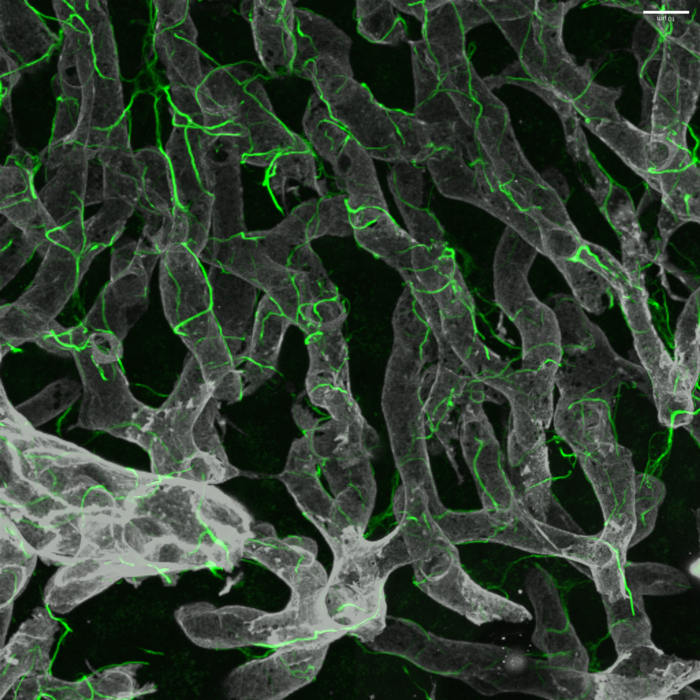

“We aimed to understand the basis of this fibrotic scarring and identify drug targets that could lead to new treatments for advanced NASH by studying hepatic stellate cells, which are the key scar-producing cells in the liver,” said senior study author Scott L. Friedman, MD, Irene and Dr. Arthur M. Fishberg Professor of Medicine, Dean for Therapeutic Discovery, and Chief of Liver Diseases at Icahn Mount Sinai. “In combining this new glass liver imaging approach—an advanced tissue clearing method that enables deep insight—along with gene expression analysis in individual stellate cells, we have unveiled an entirely new understanding of how these cells generate scarring as NASH advances to late stages.”

The researchers discovered that in advanced disease, stellate cells develop a dense network, or meshwork, of interactions among themselves that facilitate these 68 unique interaction pairs not previously identified in this disease.